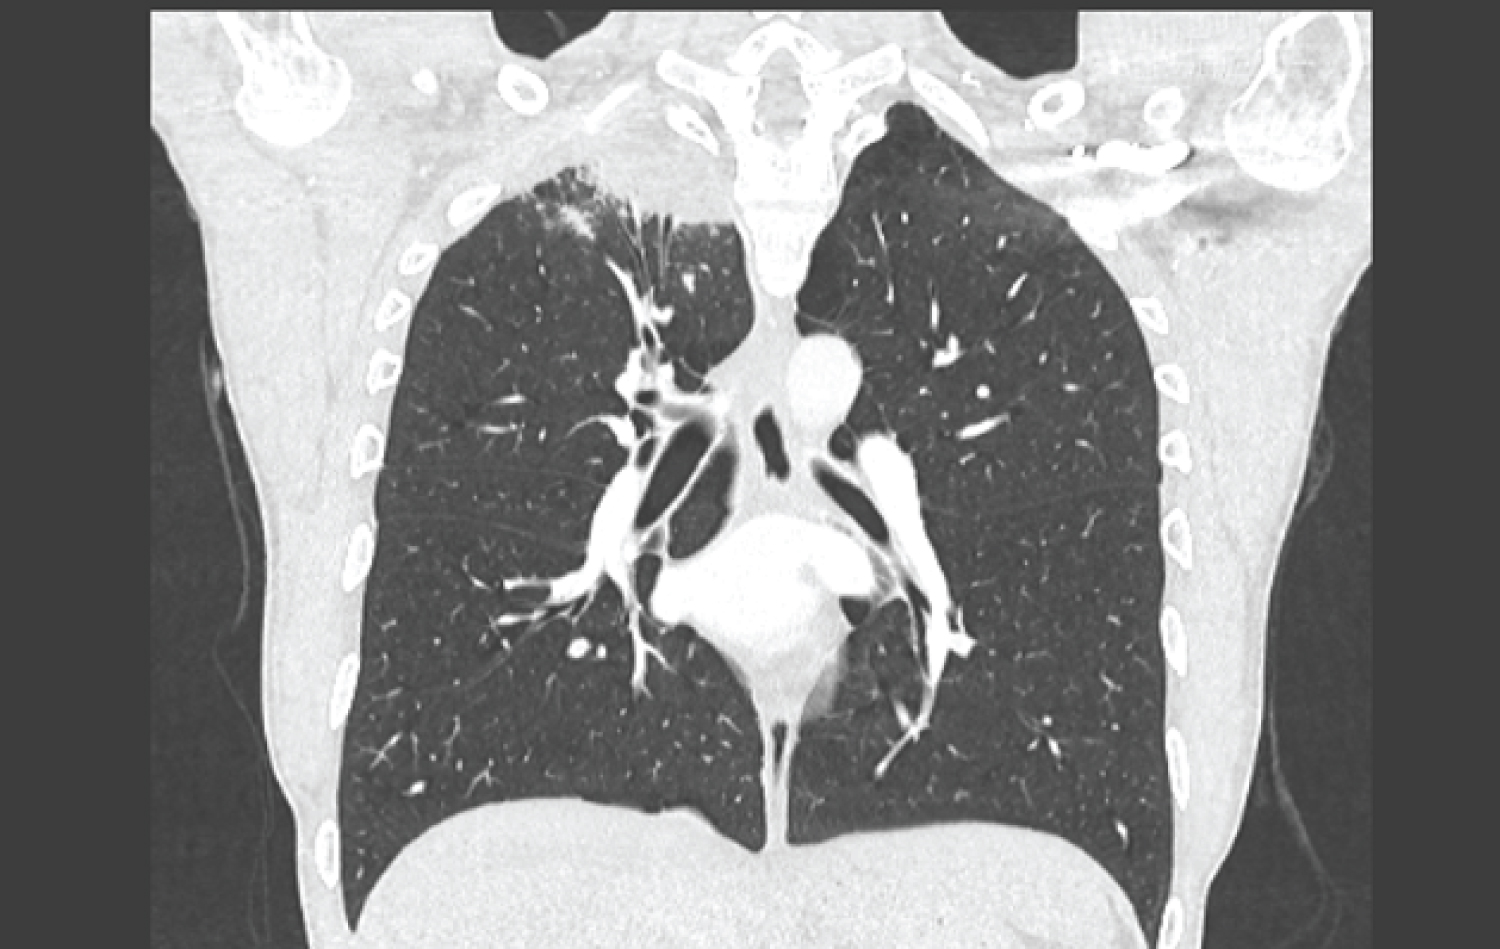

A 29-year-old man with a history of bulbar ulcer treated 2 years previously and chronic smoking at 13 packs/year was hospitalized for respiratory symptoms made up of right basithoracic pain with cough and clear sputum without fever or progressive night sweats for six months in a context of deterioration in general condition. The clinical examination was unremarkable. On the biological assessment, there was a slight inflammatory syndrome with sedimentation rate at 29 mm in the first hour and CRP at 9.8 mg/l, the blood count was normal, as were the liver and kidney assessments and the viral serologies (HBV, HCV and HIV) were negative. The search for mycobacterium tuberculosis in sputum and by gastric tube was negative on three occasions and the Quantiferon was at 2.70 IU/ml (2xN). The chest X-ray showed opacity in the apical segment of the right upper lobe. Complementary CT scan revealed significant right apical mass with alveolar condensation, pleural connections and adjacent micronodules strongly suspecting a tumor or infectious localization (Figure 1 and Figure 2). A transparietal biopsy was then performed.

Figure 1: Coronal thoracic CT section showing right apical lung mass.